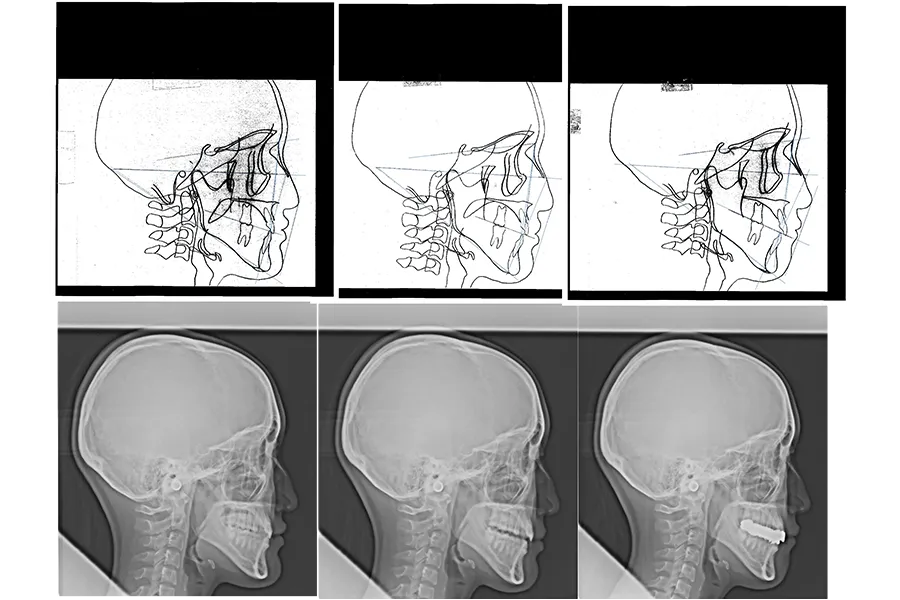

セファロ分析による評価

本症例では治療前後でセファロ分析を行い、咬合高径の変化や顎顔面バランスの変化を評価しました。

術前にはやや下顎の前突傾向があった状態が咬合挙上により改善され、側貌が改善されています。